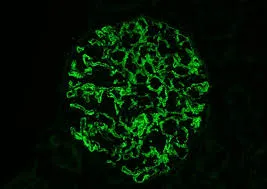

Prurido na DRC: passo a passo prático que funciona

Prurido na DRC: passo a passo prático que funciona

Será que o tratamento de Prurido na Hemodiálise deve se concentrar apenas no controle do Fósforo? Confere dicas simples e práticas de como seguir o tratamento